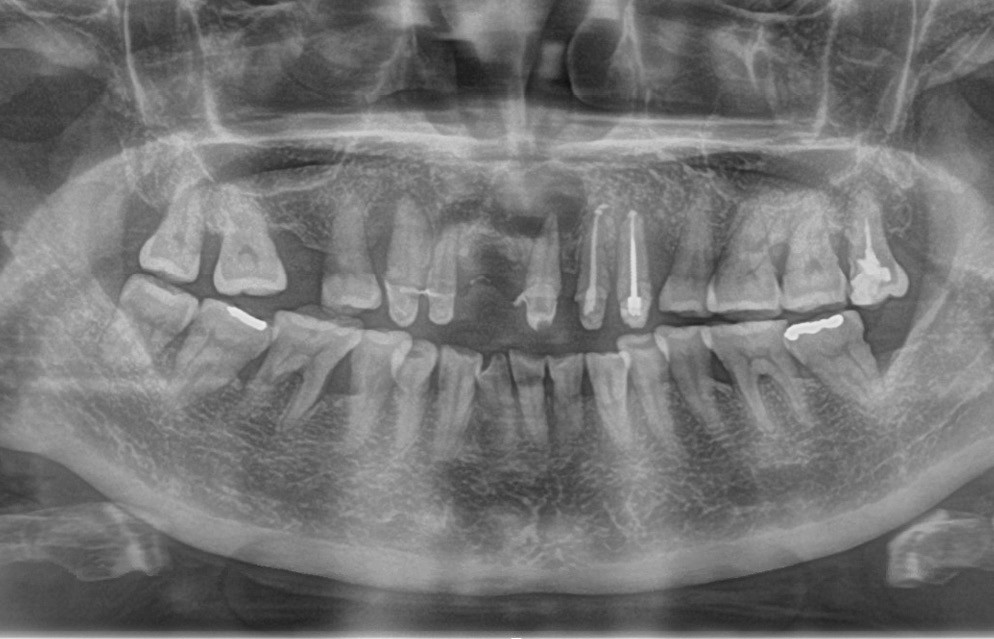

Le kyste radiculo-dentaire (fig. 1 et 2), également retrouvé sous le terme de kyste apico-dentaire, ou radiculaire, est le plus fréquent des kystes des maxillaires [1]. Il s’intègre dans la grande famille des tumeurs bénignes osseuses odontogéniques et maxillo-faciales (classification internationale de l’OMS, 2017). Il se développe aux dépens d’un granulome péri-apical secondaire à une nécrose dentaire. Le mécanisme physiopathologique à l’origine de la formation kystique est la prolifération de débris épithéliaux (débris de Malassez) présents dans le desmodonte sous l’action de stimuli inflammatoires. Un kyste est constitué d’une membrane épithéliale et d’une cavité plus ou moins liquidienne, voire solide dans certains cas. On y retrouve des cristaux de cholestérol, des calcifications dystrophiques d’exsudat inflammatoire, des macrophages, des plasmocytes, des cellules ciliées, muqueuses, géantes multinuclées et, dans certains cas, des globules rouges.

On distingue classiquement le granulome (- 1 cm) du kyste (+ 1 cm). Ce dernier possède des parois propres et des contours réguliers bien délimités. Le développement kystique s’accompagne volontiers d’un refoulement des structures avoisinantes, les corticales osseuses apparaissent soufflées, dans certains cas, amincies, pouvant venir empiéter sur des éléments anatomiques de la sphère maxillo-mandibulaire (sinus, canal mandibulaire, fosses nasales, foramen mentonnier…) (fig. 3).

Dans la majorité des cas, l’énucléation kystique s’accompagne de l’extraction de la dent causale. Toutefois, en présence de dent conservable sur le plan prothétique, une chirurgie endodontique (obturation a retro…